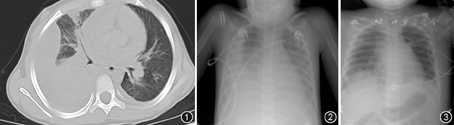

患儿入院当天血气分析pH:7.53,氧分压(PO2) 7.85 kPa,二氧化碳分压(PCO2) 4.39 kPa,碱剩余(BE) 5 mmol/L,降钙素原2 μg/L,CRP 153 mg/L,D–二聚体3.015 mg/L,余正常。冷凝集实验1∶128(+),肺炎支原体抗体1∶256。胸部CT:双肺炎症,右肺实变伴胸腔积液(图1)。冷凝集试验及肺炎支原体抗体结果支持支原体感染,CRP及降钙素原明显增高,提示合并细菌感染。外院曾给予多种头孢类抗生素及阿奇霉素治疗,考虑存在耐药菌感染,给予美罗培南联合红霉素抗感染治疗。

入院第2天,患儿双肺出现较多中小水泡音,并且面部、腹部、四肢水肿,考虑出现系统性毛细血管渗漏,给予输注羟乙基淀粉堵漏、维持循环。查血常规:Hb 63 g/L、PLT 77×109/L,WBC 19.03×109/L,中性粒细胞0.824。尿常规:隐血+、蛋白++。生化系列:总蛋白43.10 g/L、白蛋白20.52 g/L、总胆红素13.1 μmol/L、间接胆红素7.9 μmol/L、天冬氨酸转氨酶85 IU/L、丙氨酸转氨酶10 IU/L、肌酐47 μmol/L、尿素氮4.91 mmol/L、乳酸脱氢酶1 290 IU/L;红细胞沉降率36 mm/1 h。予输注白蛋白、补钾,第3天复查胸X线(图2)较前无明显好转,胸部超声提示左侧胸腔积液,考虑不排除存在耐药球菌感染,加用万古霉素。第4天,患儿出现面色苍黄,巩膜黄染,呼吸急促,约60次/min,鼻翼扇动,吸气三凹征阳性,心率140次/min左右,心音有力,各瓣膜听诊区未闻及杂音,肝脏肋下3 cm,剑突下5 cm,质韧,脾肋下2 cm,质韧。血常规:RBC 0.72×1012/L、Hb 44 g/L,PLT 142×109/L,网织红细胞0.015 7,Coombs试验+,尿常规:隐血(++),蛋白(+)。总蛋白46.25 g/L、白蛋白25.73 g/L、总胆红素43.6 μmol/L、间接胆红素35.8 μmol/L、天冬氨酸转氨酶108 IU/L、丙氨酸转氨酶11 IU/L、肌酐41.6 μmol/L、尿素氮4.69 mmol/L,床旁B超提示双肾实质回声增强,腹腔积液。骨髓细胞学检查提示感染骨髓象,粒系胞质见紫红色较粗中毒颗粒,红系增生相对偏低,占16.8%。考虑患儿严重贫血,组织供氧不足,拟输注洗涤红细胞,但患儿血型鉴定困难,反复配血不成功。给予了冲击剂量的甲泼尼龙20 mg/kg及人免疫球蛋白1 g/(kg·d),2次。第5天,RBC降至0.60×1012/L、Hb 28 g/L,网织红细胞0.022 9。患儿出现神志恍惚,烦躁不安,端坐呼吸,持续鼻导管吸氧下血氧饱和度(SPO2)降至0.75~0.80,立即给予机械正压通气,气管插管时见有粉红色泡沫样痰涌出,并发急性呼吸衰竭、心力衰竭。当日再次交叉配血成功,连输洗涤红细胞3 d。第6天,患儿Hb升至42 g/L,第7天升至61 g/L,第8天升至70 g/L,网织红细胞0.155 0,心力衰竭逐渐纠正、溶血渐停止,机械通气6 d,复查X线片明显好转(图3),予停用呼吸机,拔除气管插管。住院26 d,Hb逐渐升至102 g/L,网织红细胞降至0.076 0,周身水肿逐渐消退,体温正常,治愈出院。最近一次复查Hb 125 g/L左右,无任何后遗症。